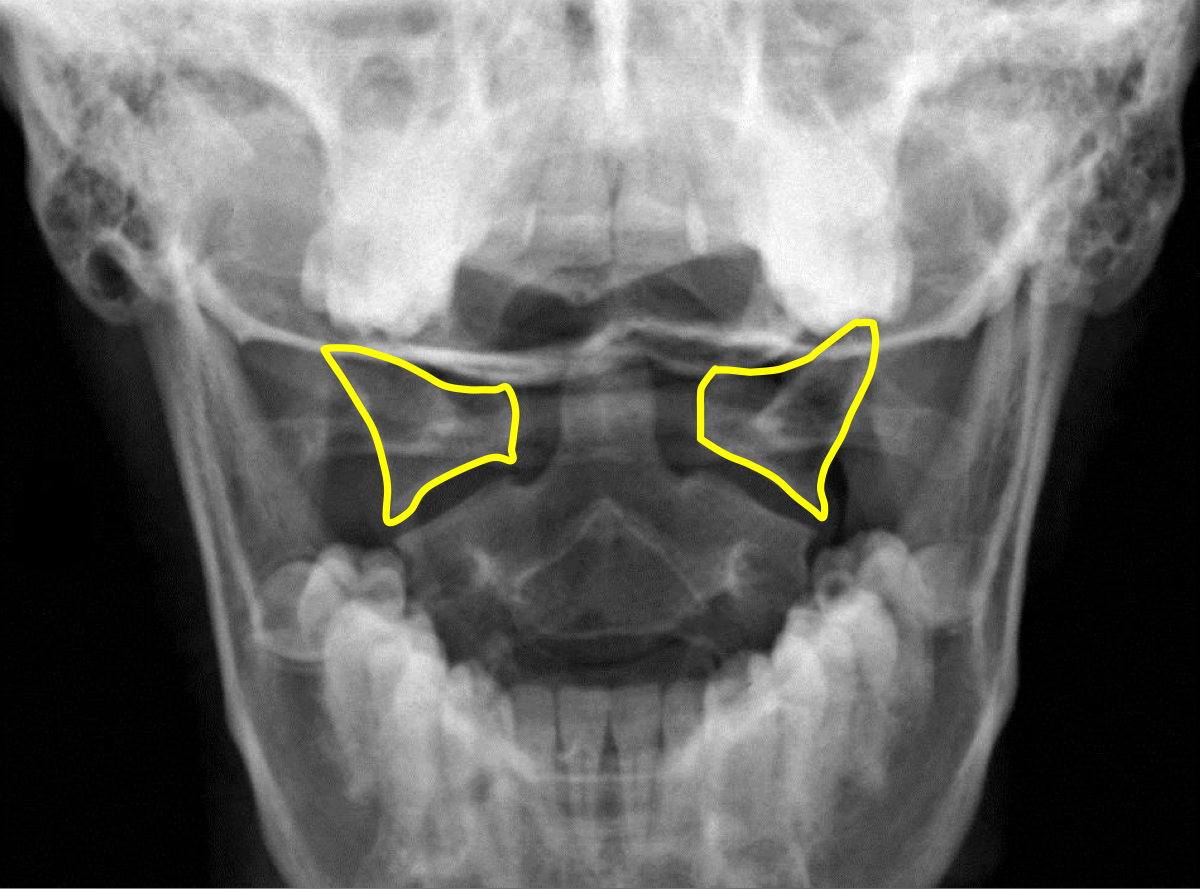

What view is this?

APOM

What is this?

C1 Lateral Masses

What is this?

Mastoid Processes

What is this - Yellow?

Occipital Condyles

What is this - blue?

Foramen Magnum

What is this?

C1 TVP/Lateral Mass Junction

What is this?

Odontoid Process

What is this?

C2 Spinous Process

What is this?

C2 Pedicle Shadows